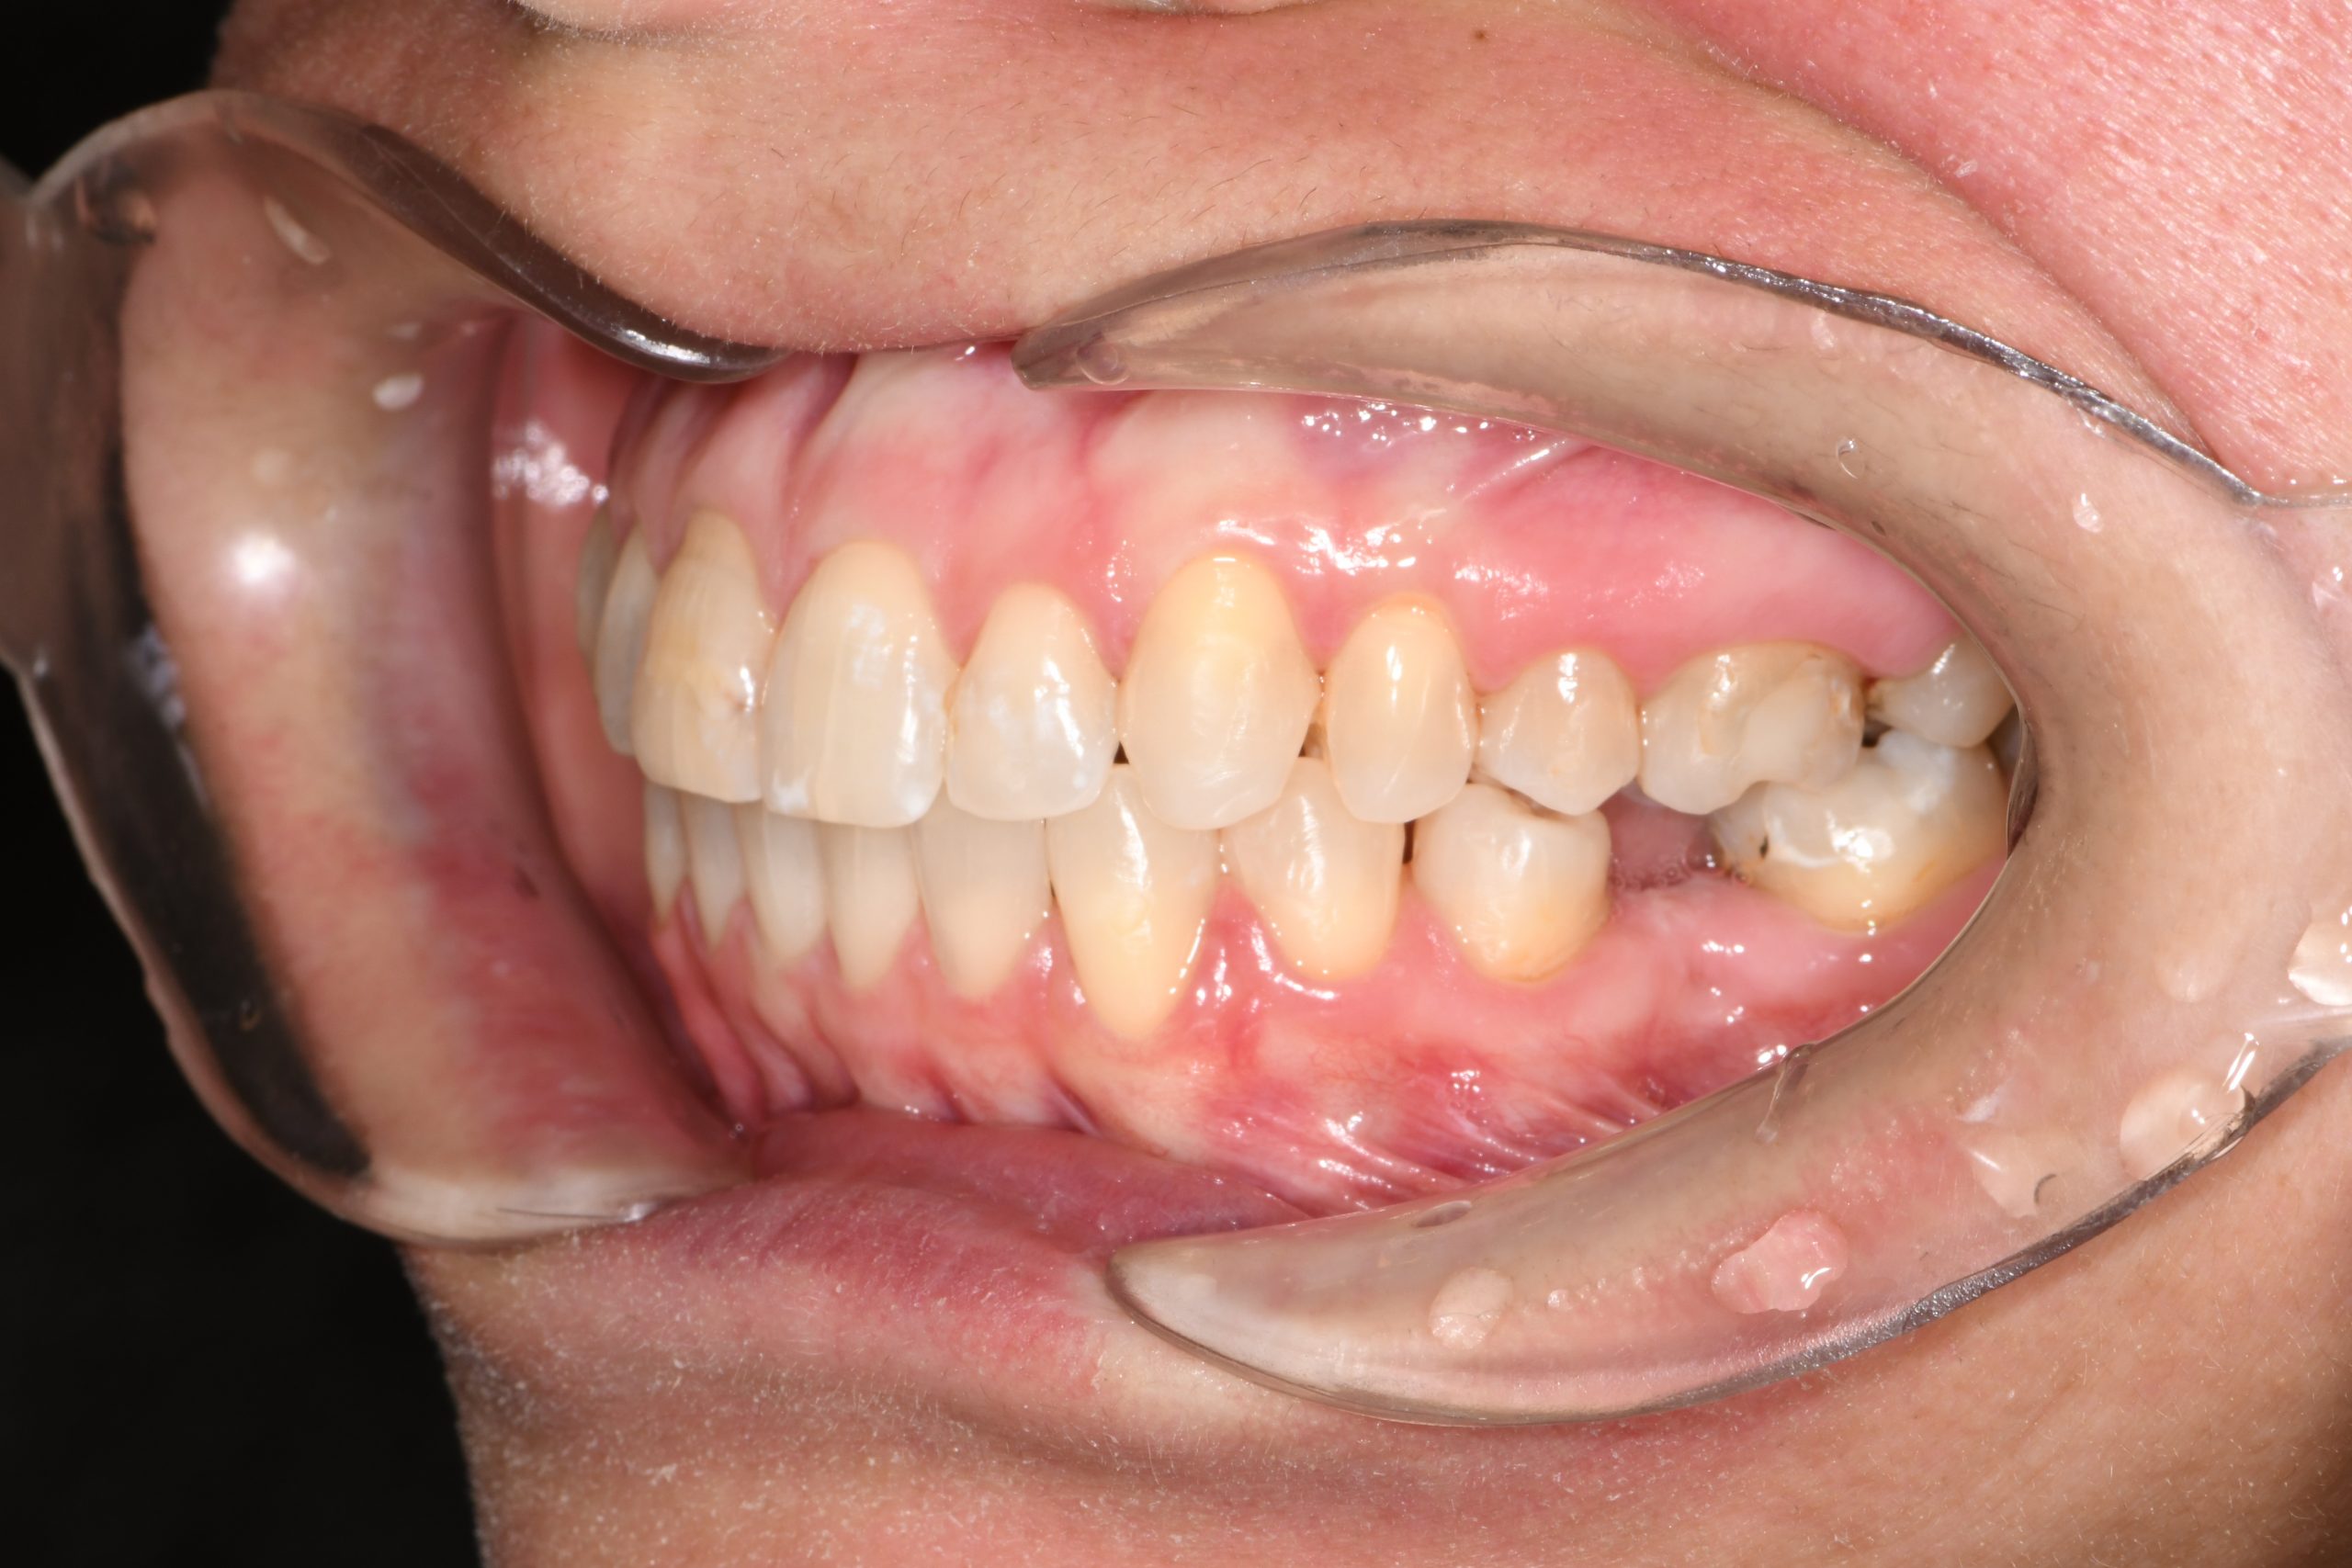

Az elmúlt évekből rengeteg szakmai referenciát tudnánk bemutatni, amelyek különböző fogszabályozási problémákat oldottak meg. Válogatva a több száz esetből, ezen az oldalon olyan képeket, információkat igyekeztünk bemutatni, amelyeknek a segítségével a jövőbeni pácienseinknek azt tudjuk üzenni: A Te fogsorod is lehet gyönyörű!